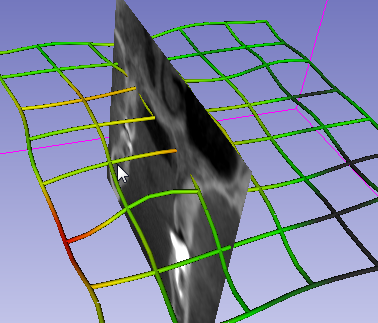

Import the sample microCT stack (or load the NRRD, if you already saved it) into a blank scene. Switch to the Transforms module

- Put the volume under a blank transform and try using the rotation sliders to change the slice views. Explore other options of the transform module. See that if you remove the 3D volume out of the transformation, slice views go back to original orientation

CropVolumeand create a new ROI that covers the extend of the data, then go toTransformsmodule and assign the new ROI tho this transform node. Use sliders to rotate the ROI approximately 45 degrees (in any plane is fine). Now go back toCrop Volumeand do a cropping. What happened?